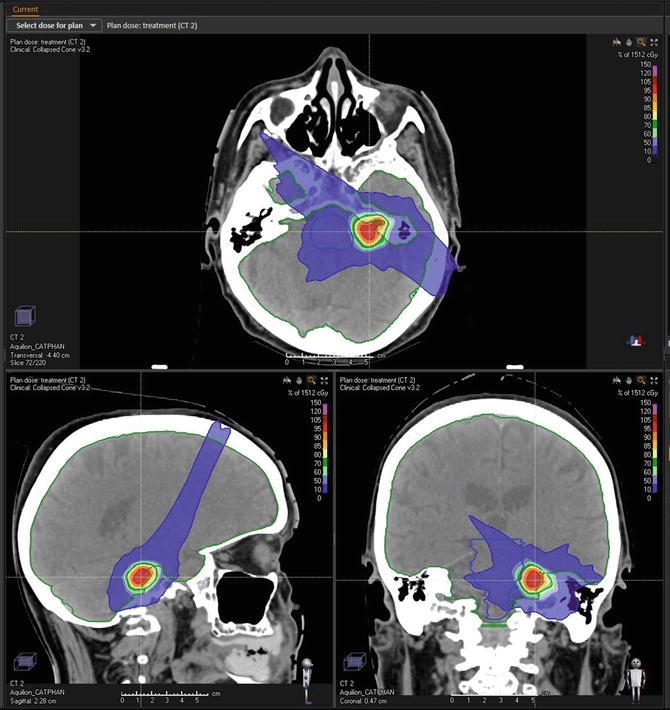

2. Conformal gamma knife radiosurgery dose plan for acoustic neuroma Radiosurgery Acoustic Neuroma Although benign, acoustic neuromas can impact patients' quality of life significantly. Radiosurgical treatment for acoustic neuroma is an alternative to microsurgery. Specialists at nyu langone may use stereotactic radiosurgery to stop the growth of an acoustic neuroma, also called vestibular schwannoma. It is associated with a lower rate of immediate and. We use three types of radiation for acoustic neuroma:. Radiosurgery Acoustic Neuroma.